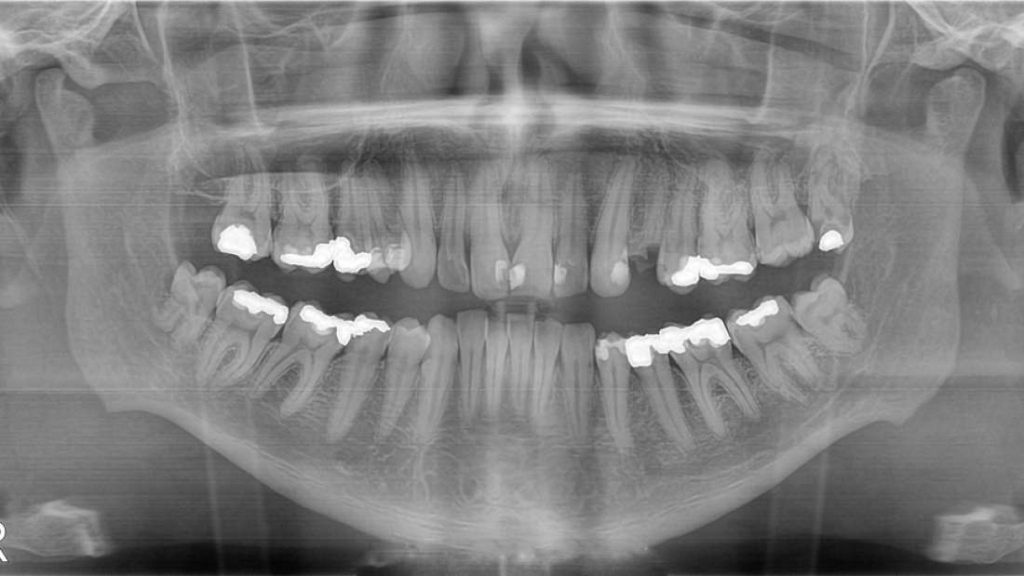

Dentistas podem tratar cárie dentária e cavidades, a solução nem sempre é satisfatória. Cimentos atuais usados para preencher os buracos podem rachar ou desintegrar, muitas vezes levando a repetidos trabalhos para as piores cavidades. Eventualmente, pode mesmo ser obrigado a remover o dente, pois o furo pode nunca ser inteiramente tratado.

Mas ao tratar as cavidades com uma droga já estabelecida, conhecida como tideglusib, os pesquisadores conseguiram fazer algo notável.

Com o passar do tempo, a esponja degradou-se e foi substituída por dentina recém-sintetizada, efetivamente um trabalho de reparo natural pelas próprias células-tronco do dente.